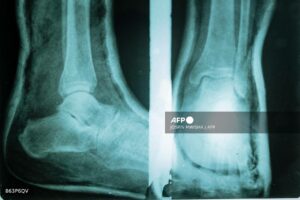

Feet, hands, metal bars and pins — entire limbs are reconstructed.

Plastic sheets are softened in an oven before being shaped and cooled. But too often the centre lacks the materials needed, as well as qualified technicians.